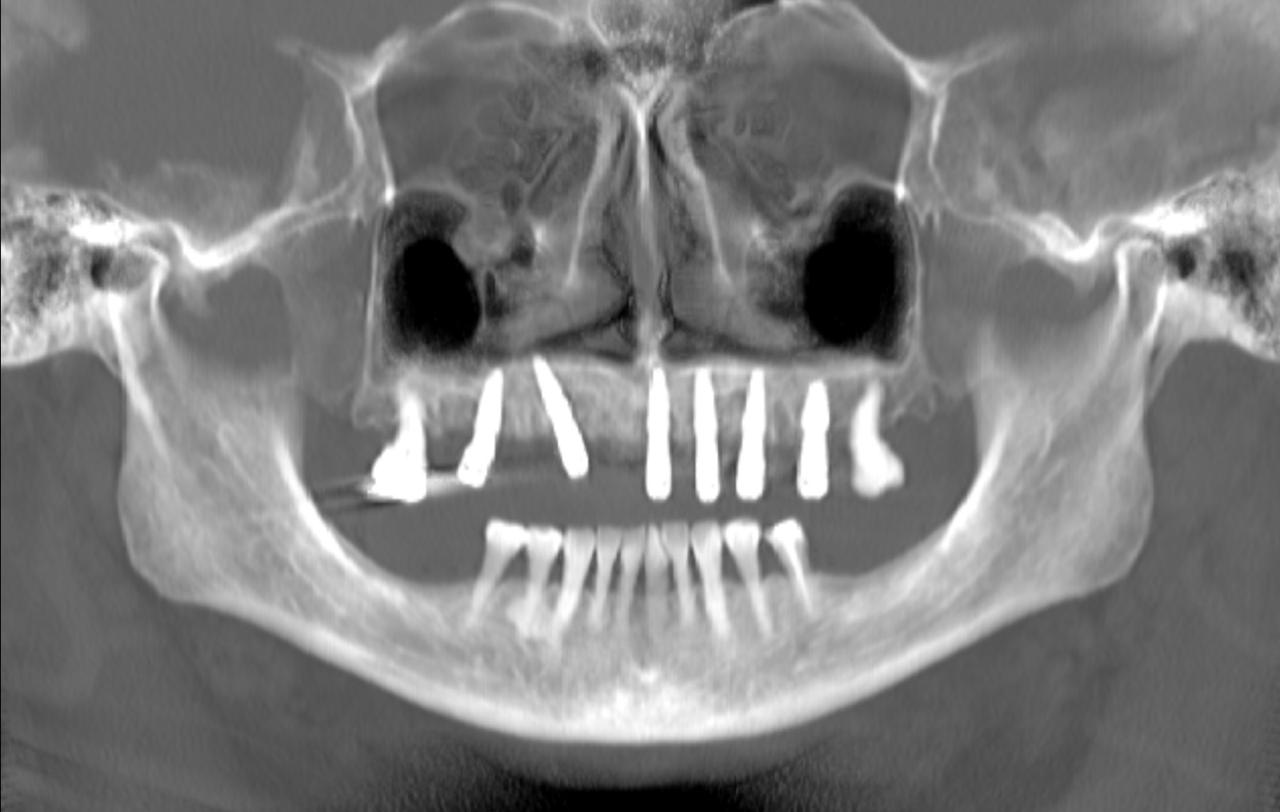

La intervención se realizó bajo anestesia general y contempló la extracción de la totalidad de los dientes del maxilar superior debido a una enfermedad periodontal avanzada, junto con la instalación simultánea de seis implantes dentales mediante cirugía guiada por planificación digital. En este caso, no se efectuó carga inmediata: el plan considera una carga temprana dentro del proceso de rehabilitación.

Uno de los aspectos más destacados fue que, en el mismo acto quirúrgico, se realizó la toma de la impresión para enviar a confeccionar una estructura provisoria completa (con la totalidad de los dientes maxilares), diseñada y elaborada mediante un proceso digital, lo que permite acortar tiempos y aumentar la precisión en etapas clave del tratamiento.